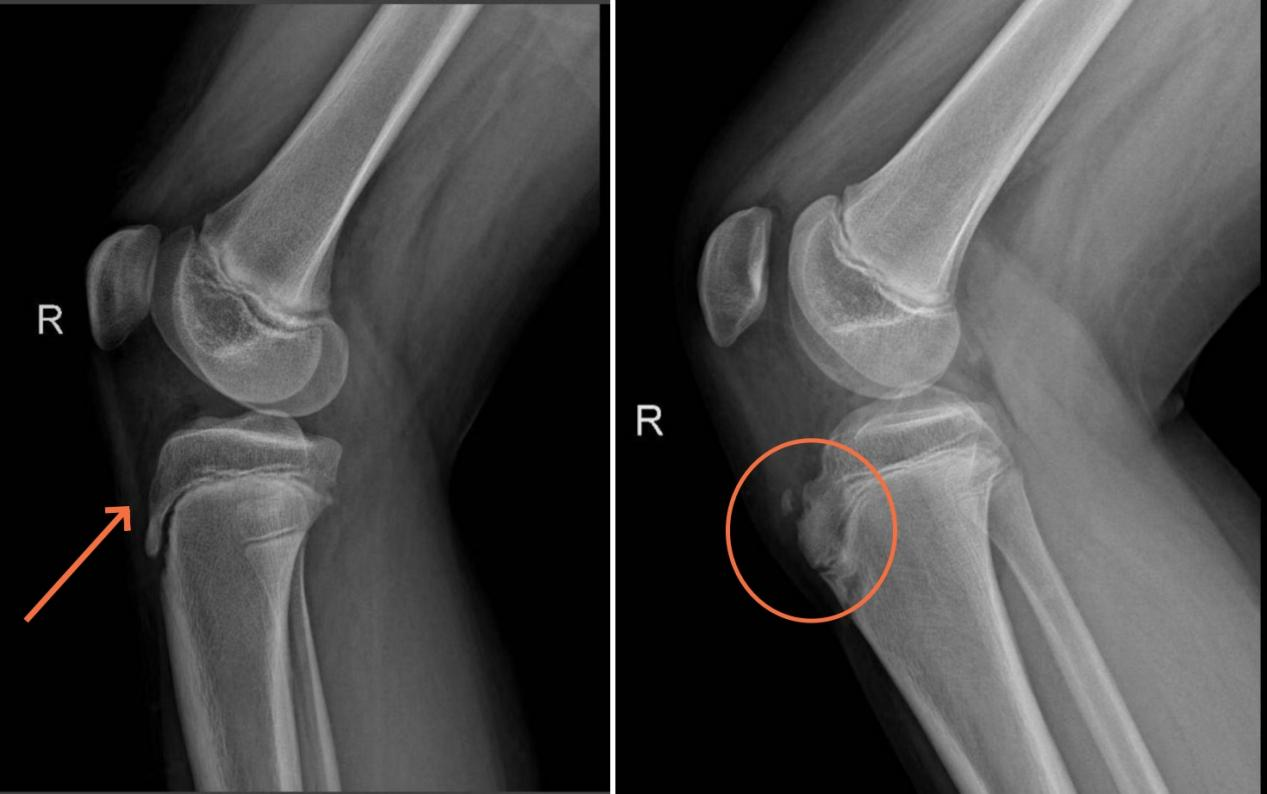

左图为正常的青少年胫骨结节,右图为病变的青少年胫骨结节,可见明显凸起。